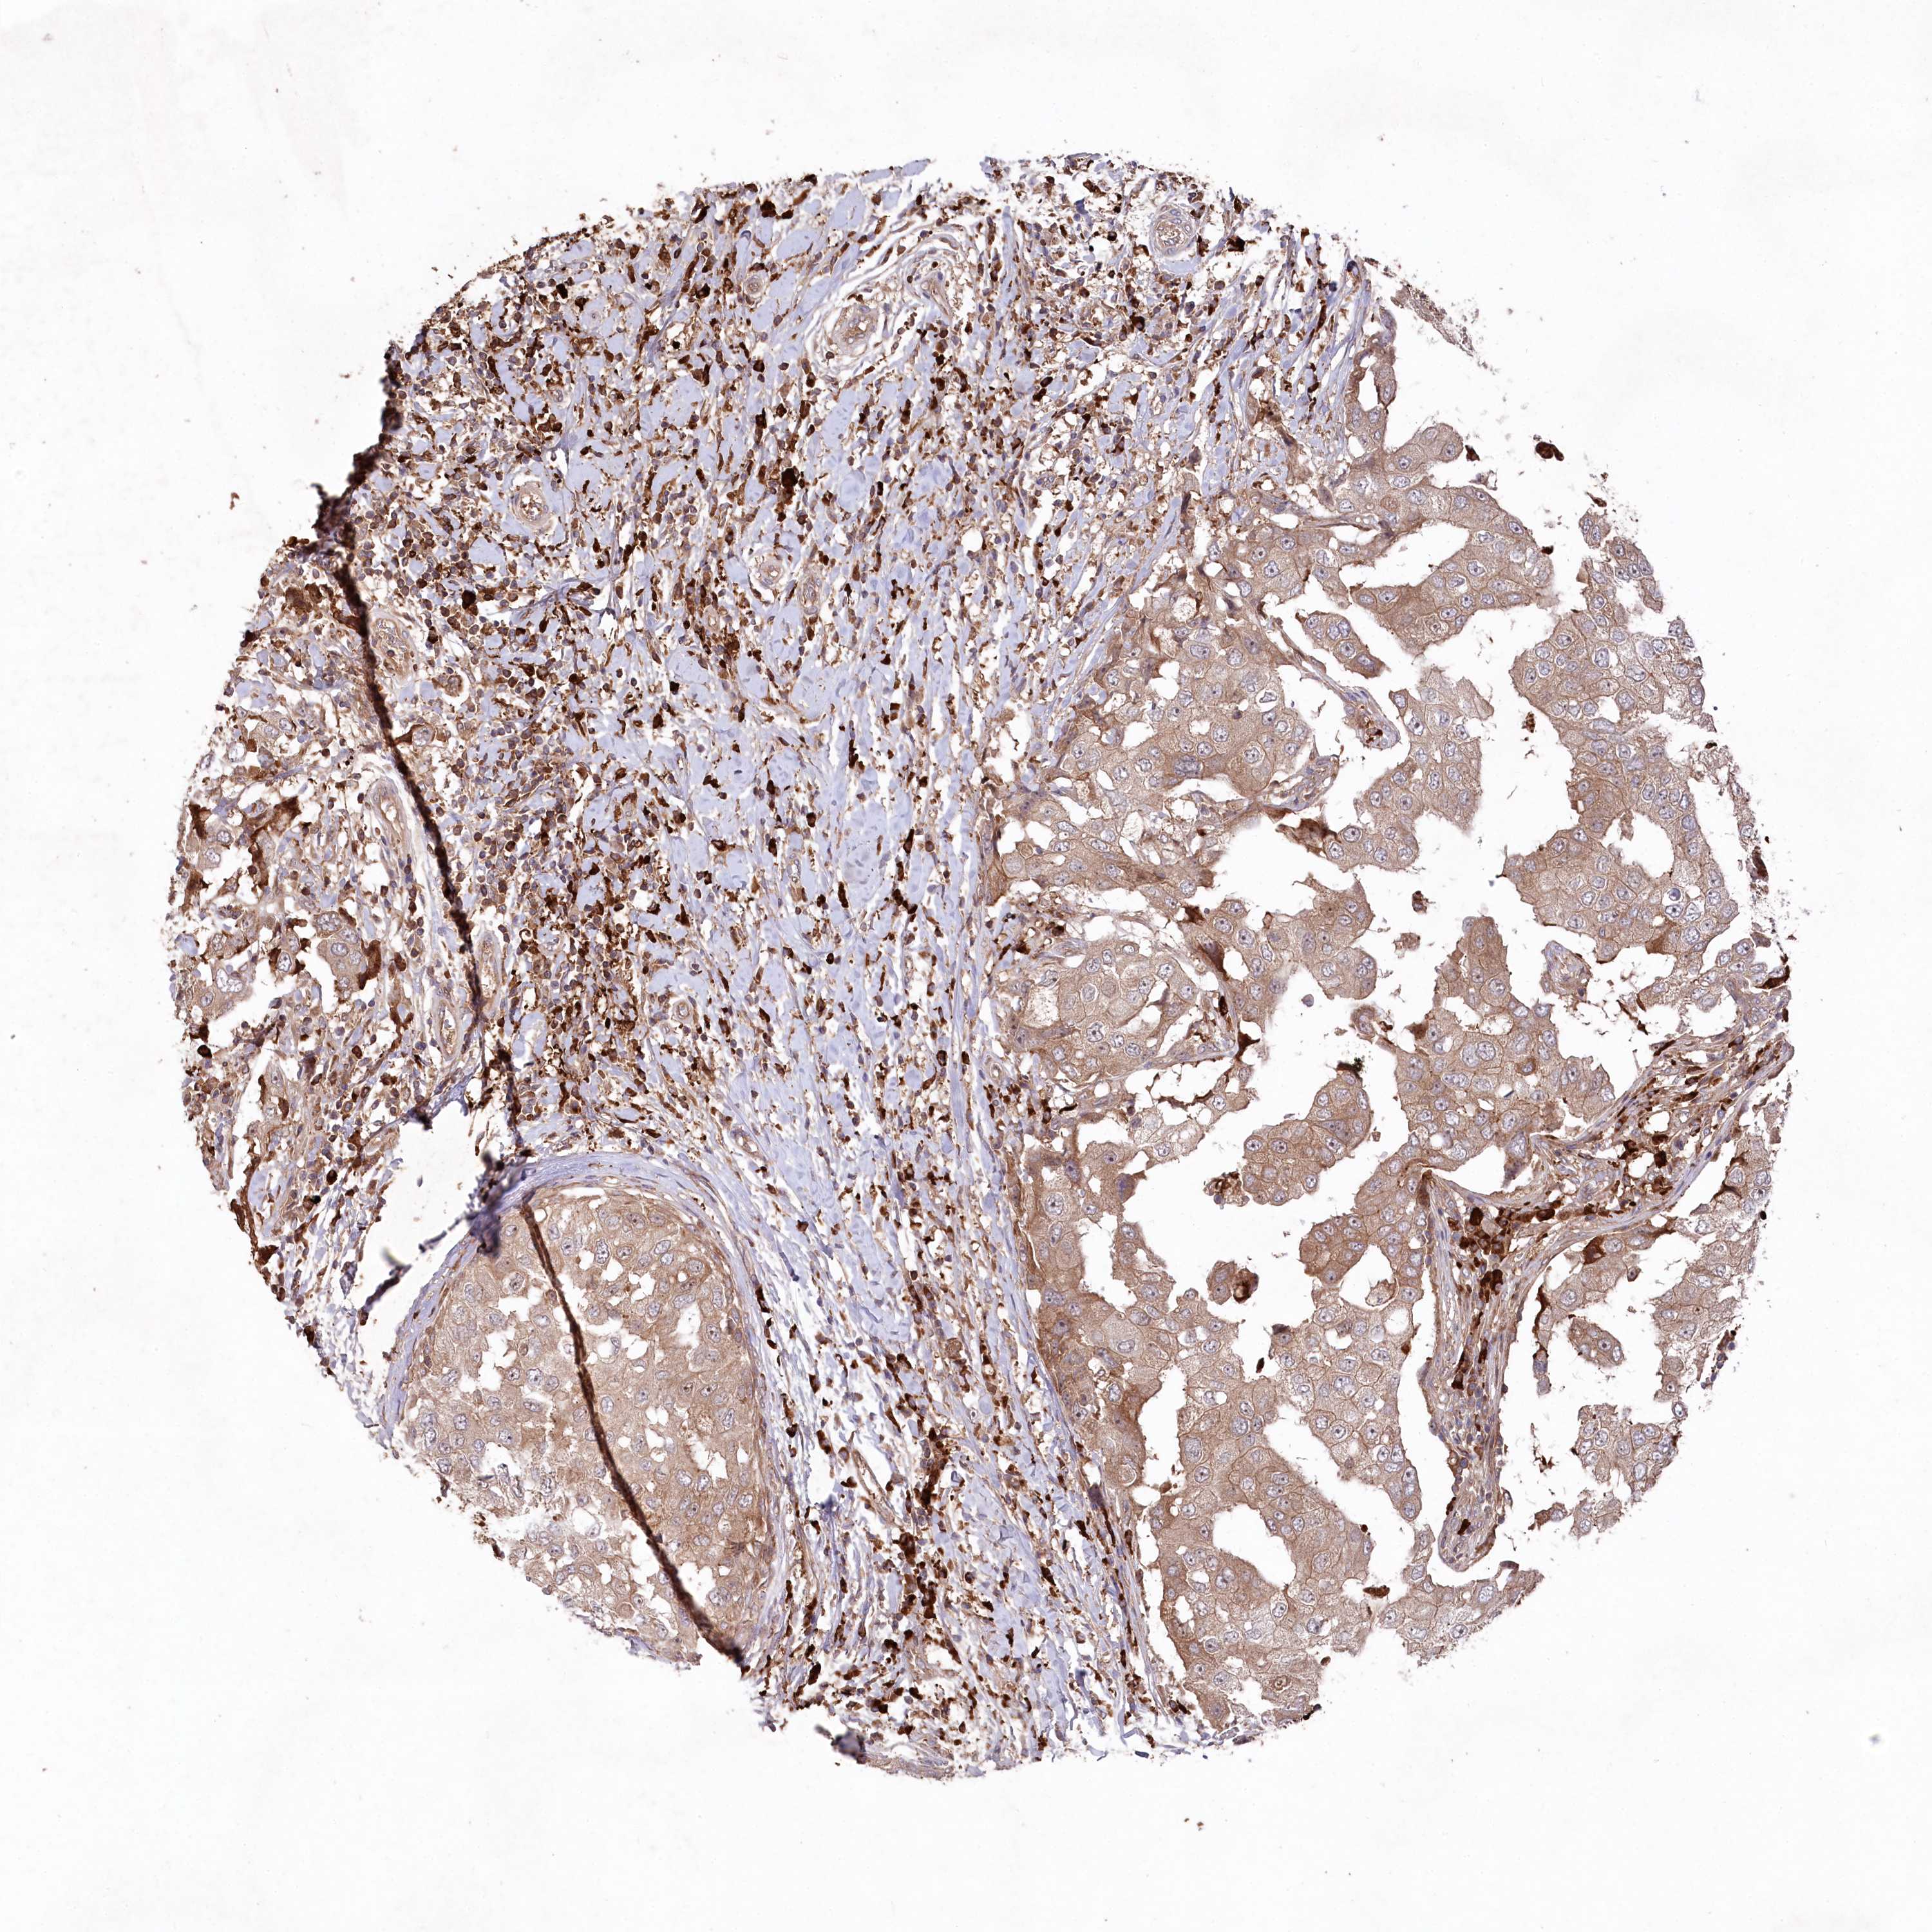

CANCER BREAST CANCER Show tissue menu

BRCA TCGA BRCA VALIDATION PROTEIN EXPRESSION

ANTIBODIES

AND

VALIDATION